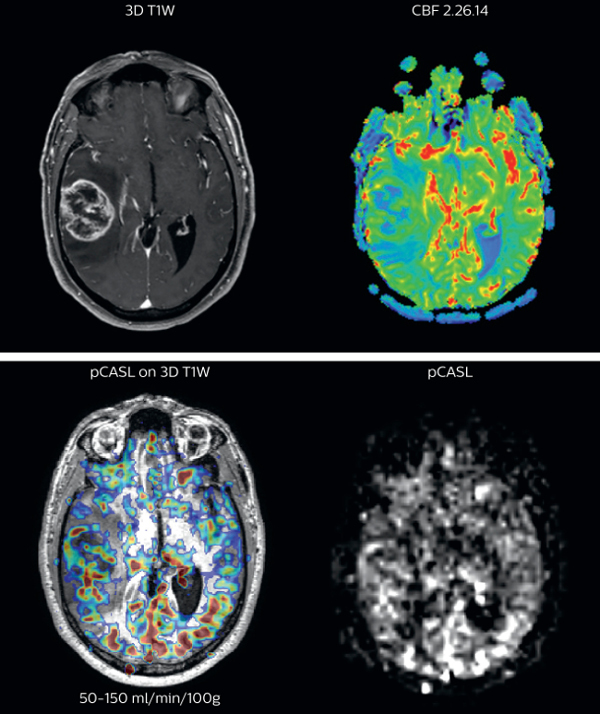

Cerebral blood flow in glioblastoma

The pCASL perfusion map overlaid on the 3D T1 image demonstrates a peripheral rim of elevated cerebral blood flow corresponding to the centrally necrotic glioblastoma.

The pCASL-generated CBF closely approximates the rim of elevated rCBV obtained with DSC contrast-enhanced perfusion imaging.

Scanned on Achieva 3.0T dStream

Brain perfusion imaging is typically performed using a contrast agent. However, pCASL allows visualization of brain perfusion and physiology without contrast agent injection. This fast sequence can be an alternative for perfusion imaging in patients who are contraindicated for use of gadolinium based contrast agents.

“We have compared pCASL to T2*-weighted perfusion imaging with contrast agent in patientswith brain tumors”, says Dr. Nickerson. “In the cases included in our study, pCASL was at least as representative as perfusion with contrast agent. It’s a pretty big improvement if we’re avoiding giving gadolinium and we’re getting a quite equivalent dataset, that’s a pretty big improvement.”

pCASL broadly used in brain tumor patients

The pCASL method is now broadly used at UVM. “It’s a short sequence, and is ideal for use in patients where motion is a concern. pCASL is currently included in all our MRI exams for patients with a known tumor, either initial or post-operative and all follow-ups. Additionally, it can also be used when we examine for stroke. And of course, pCASL is an alternative allowing perfusion imaging in patients with compromised renal systems, for whom contrast agent is contraindicated.”

“Furthermore, we image a fair number of pediatric tumors here and the repeatability of pCASL is a great benefit when scanning pediatric patients with brain tumors. If the patient moves during the acquisition of a DSC perfusion scan, we missed our shot. However, if a patient moves during pCASL, we can simply repeat the scan because there’s no contrast injection involved,” says Dr. Nickerson

Richard Watts, PhD, brings forward another aspect. “Quantification with pCASL does not have the issue of selecting an arterial input function like with contrast-agent based scans. In the brain tumor studies that we’ve been running, we feel it’s not sufficient just to ascertain one side has got more blood flow than the other side. In the future, we want to move towards quantitative comparisons between subjects.”